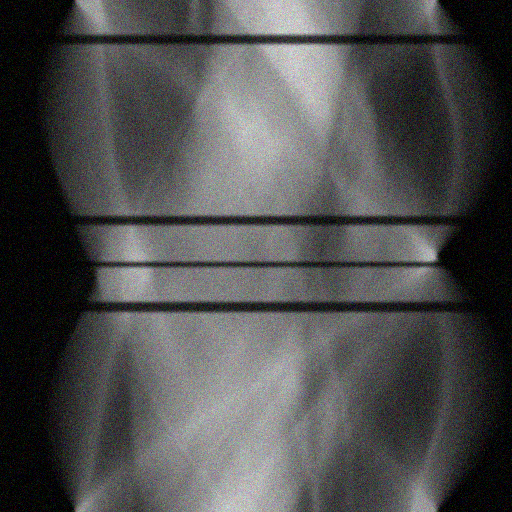

Figure 2: Qualitative inpainting results on TomoBank (lines 1 to 2) and LoDoPaB (lines 3 to 4) with random mask (ratio = 0.8) at 1024×\times1024 resolution. Odd columns and even columns show the sinograms and reconstructed images, respectively.

Inpainting Quality. Tab 2 summarizes accuracy results. At 2048×\times2048 resolution, HiSin achieves the best performance among all baselines while remaining memory-efficient, demonstrating its ability to extend high-quality inpainting to resolutions where other diffusion models fail. At 1024×\times1024, HiSin delivers accuracy comparable to its computation-intensive counterpart RePaint, showing that our optimizations do not compromise fidelity at moderate scales. Compared to DiffIR and HiDiffusion, HiSin consistently achieves higher SSIM and PSNR across mask ratios, with improvements up to +0.03 SSIM and +1.8 dB PSNR. Fig 2 visualizes sinogram inpainting and reconstructed images, where HiSin produces nearly indistinguishable results from RePaint. These findings confirm that HiSin fundamentally extends diffusion-based inpainting to 2048×\times2048 resolution in a more memory- and runtime-efficient manner.